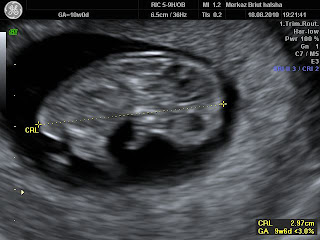

העובר נצפה לראשונה בשב' 5-6 בבדיקה וגינלית (קוטר שק הריון בין 5-12ממ'). גודל העובר בשלב זה 1-2 ממ' והוא נצפה כהתעבות חלק קטן של שק החלמון. פעילות לבבית מתחילה מוקדם מאד, כשהעובר עוד פחות מ 2ממ', אך נצפית ברוב המקרים שהעובר 4-5ממ' בשב' 7. קצב הלב איטי (יחסית) בשבוע 6, סביב 100 פעימות לדקה. הקצב גובר עד 170 בשב' 9 ולאחר מכן מתייצב סביב 140 פעימות לדקה.

![]() |

| עובר מסומן בין שתי הצלבים ושק חלמון בחץ |